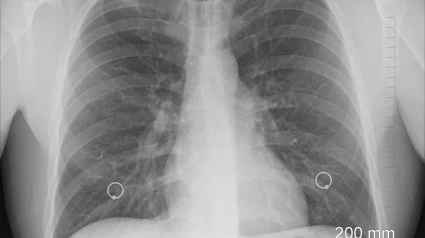

El Hospital Universitario de Jaén diagnostica cada año 300 nuevos casos de cáncer de pulmón, un tipo de tumor que provoca mayor mortalidad, tanto en hombres como en mujeres y uno de los cáncer más frecuente, como colon o mama. Esta mortalidad se relaciona, entre otros aspectos, con su frecuente diagnóstico tardío, en fases avanzadas, en las cuales las opciones terapéuticas son escasas, disminuyendo la supervivencia esperada.

Las opciones terapéuticas en estos tumores son varias, cirugía, radioterapia o tratamiento sistémicos con quimioterapia, inmunoterapia, o tratamientos dirigidos, si bien se pueden precisar una combinación de ellos. Sin embargo, cuando se diagnostica en fases precoces de la enfermedad, en las que habitualmente se puede realizar una cirugía con intención curativa, la supervivencia aumenta.

“El 75% de las intervenciones quirúrgicas a pacientes que requieren este tipo de tratamiento se realizan a través de técnicas mínimamente invasivas, lo que posibilita menor afectación y más rápida recuperación”, ha indicado el responsable de la Unidad de de Cirugía Torácica, Antonio Bravo. “Para intentar disminuir la mortalidad de este cáncer, resulta fundamental incidir en su prevención, mediante la disminución del tabaquismo, uno de los mayores factores de riesgo, si bien se está registrando el incremento del 20% en caso de personas no fumadoras, especialmente en mujeres. Además de evitar el riesgo, es fundamental el diagnóstico precoz, que, junto con la aplicación de nuevos tratamientos, mejoran la supervivencia del paciente”